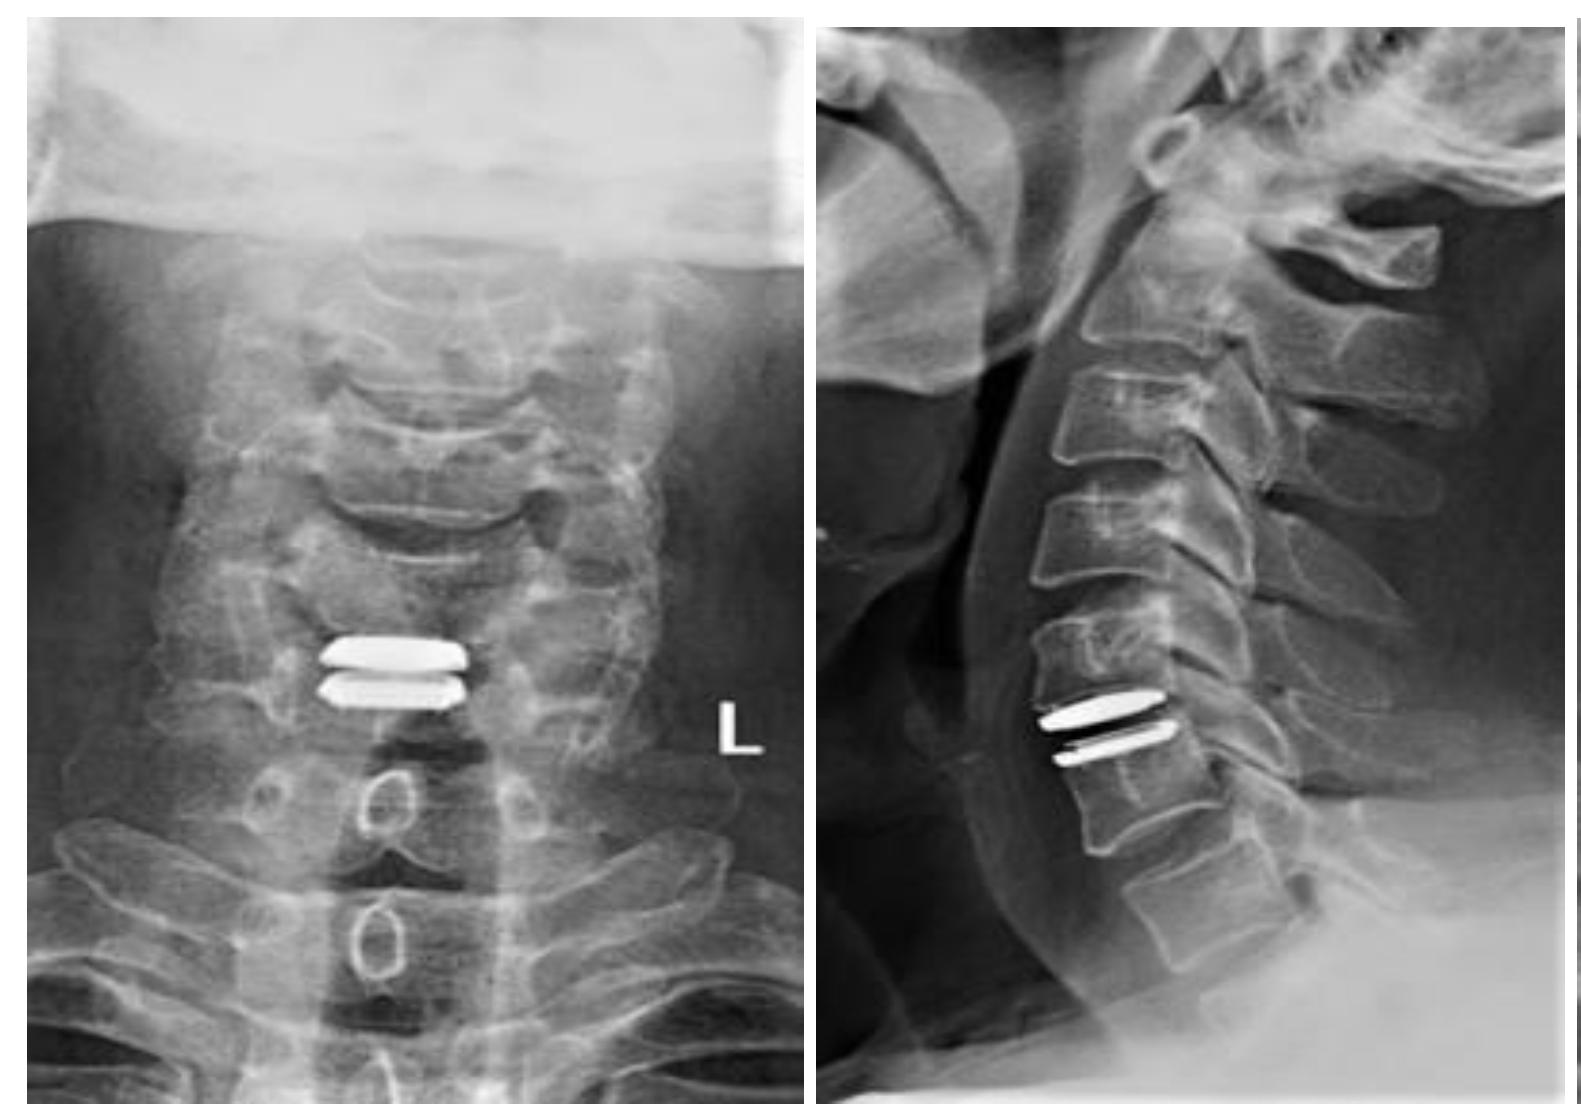

颈椎人工间盘置换术(ACDR)